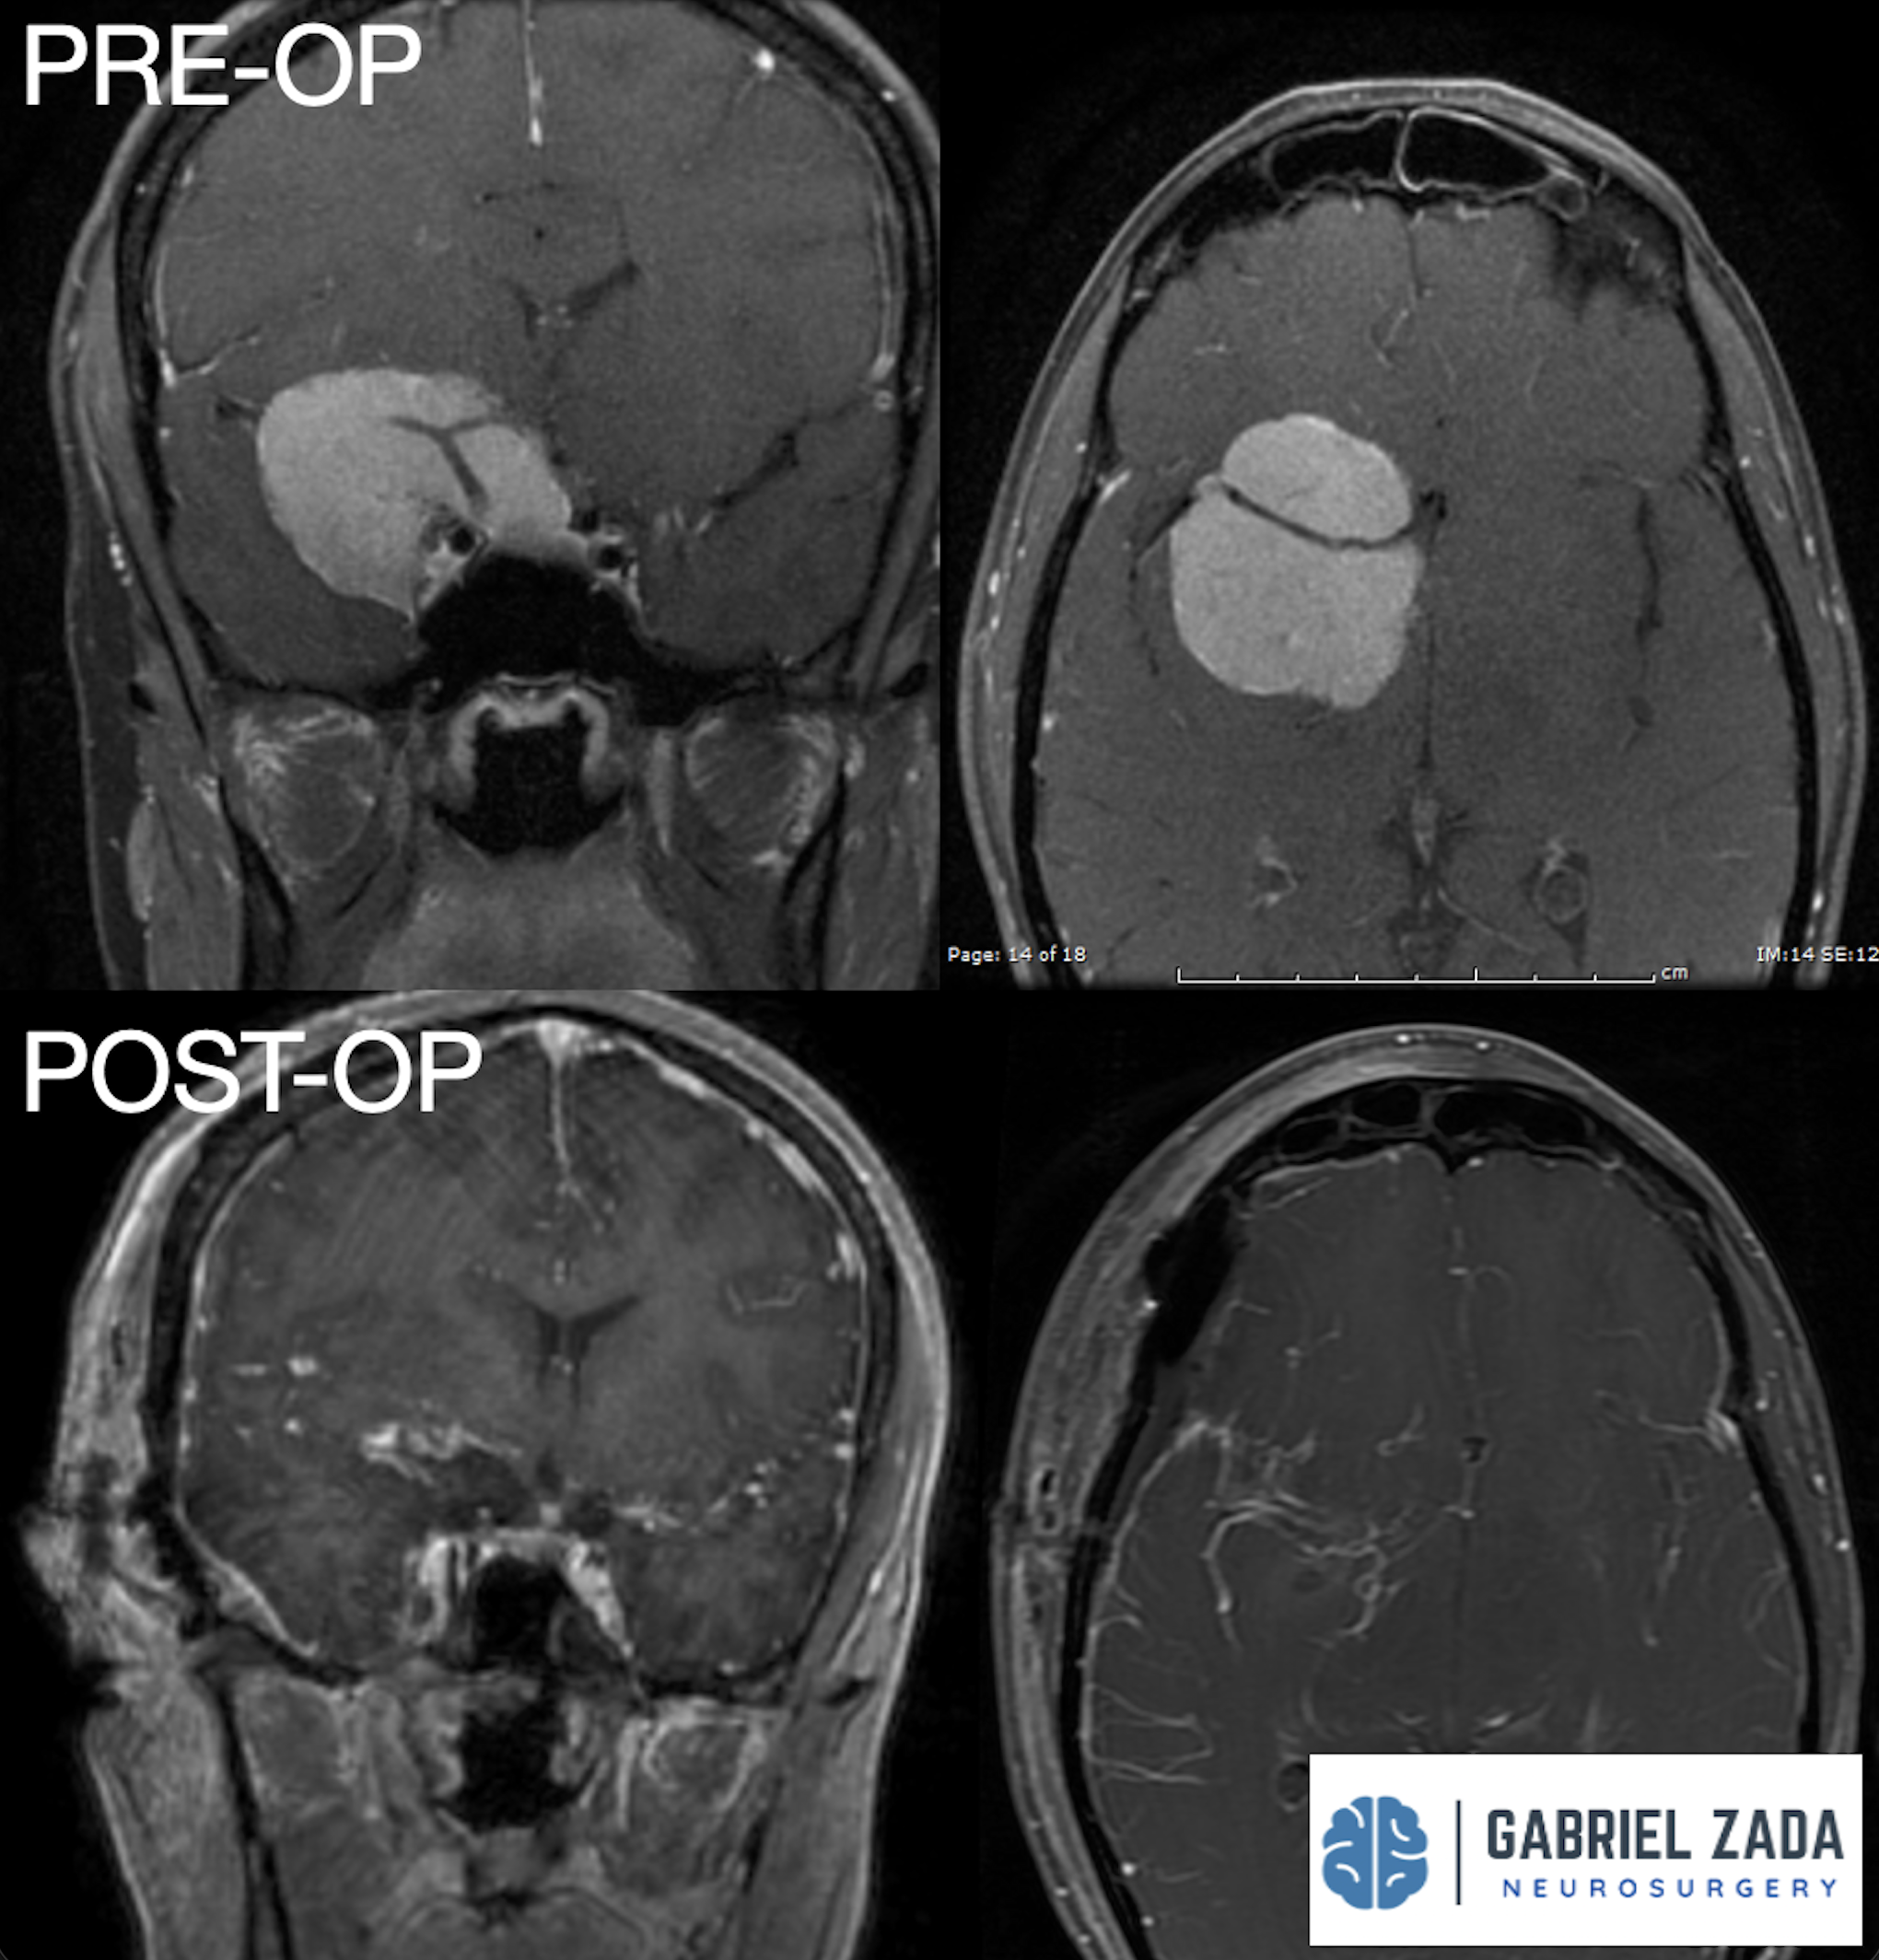

Explore this comprehensive gallery featuring pre‑ and post‑operative imaging of patients with skull‑base tumors treated by Gabriel Zada, MD, MS, FAANS, FACS. These cases highlight Dr. Zada’s expertise in advanced neurosurgical techniques and outcomes.

*Representative cases shown for educational purposes. All images de-identified. Individual results vary.